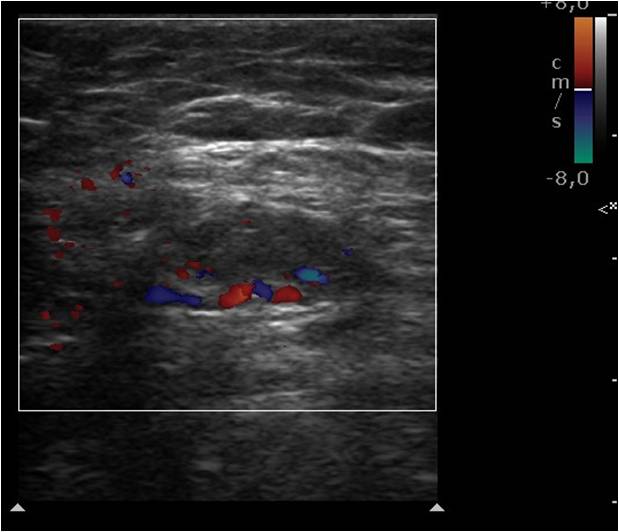

14. Hensen JH, Van Breda Vriesman AC, Puylaert JB. Abdominal wall endometriosis: clinical presentation and imaging features with emphasis on sonography. AJR Am J Roentgenol 2006;186(3):616-20.

15. Kinkel K, Frei KA, Balleyguier C, Chapron C. Diagnosis of endometriosis with imaging: a review. Eur Radiol 2006;16(2):285-98.